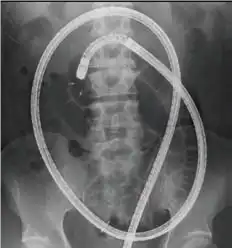

Anterograde insertion Retrograde insertion